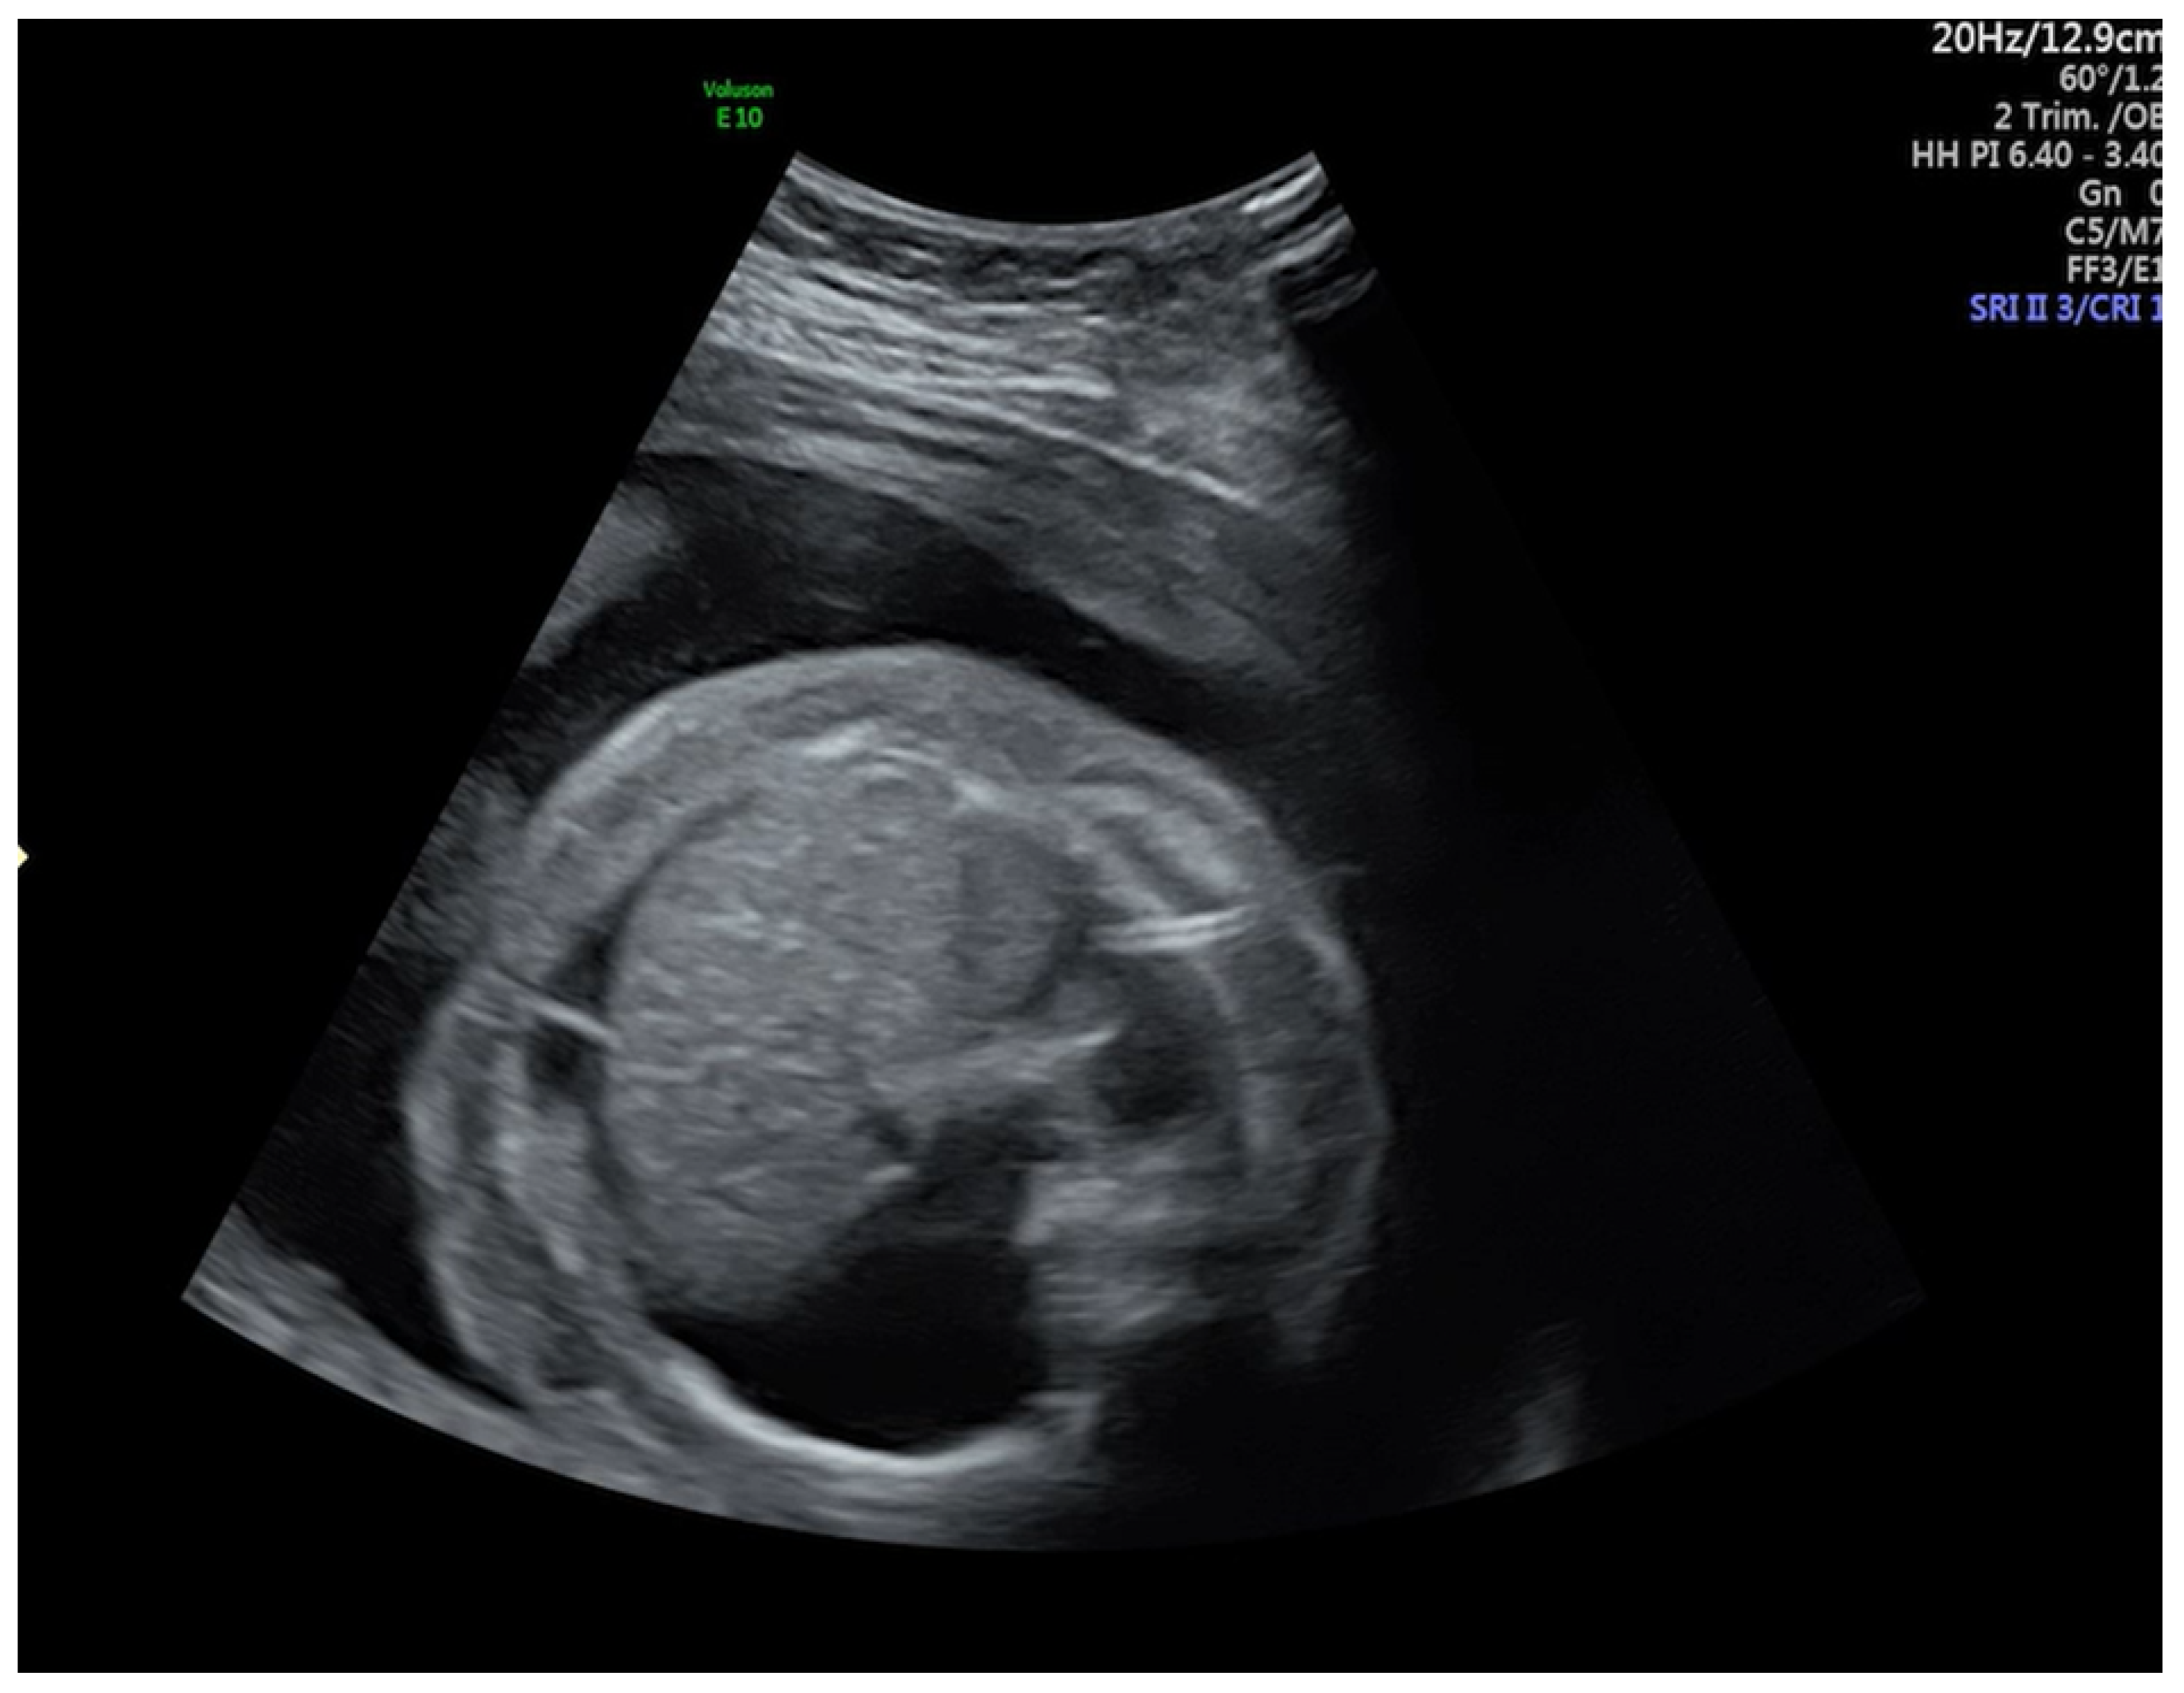

A Case of COVID-19 Pregnancy Complicated with Hydrops Fetalis and Intrauterine Death

2. Case Report